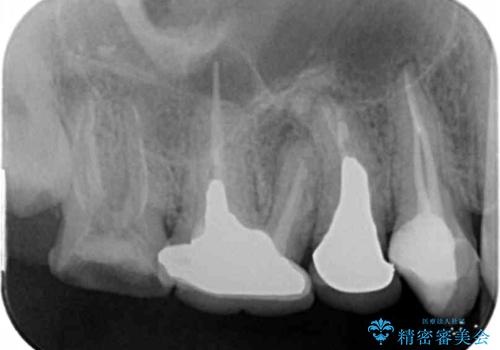

根尖病変 →マイクロスコープを用いた精密根管治療の実施

一つ一つの工程を丁寧に行うことで、根尖病変の改善傾向も見られ、安定した歯周環境を整えることができました。